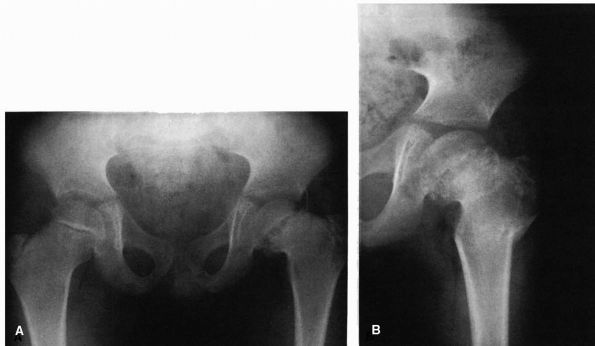

descriptive term referring to the angular relation between the femoral

head or neck, or both, and the femoral shaft, which is less than the

normal value for the patient’s age. This abnormal relation may be

congenital, developmental, or acquired. It is most important to

distinguish between these three etiologic groups because each has its

own natural history. This section deals only with developmental coxa

vara.

the cervical region of the proximal femur that are accompanied by a

widened and vertically oriented physeal plate (Figure 15-27).

The shaft of the femur is normal. Clinical and radiographic features

are not present at birth. Developmental coxa vara is an extremely rare

condition equally affecting boys and girls. About 30% of the cases are

bilateral. A familial tendency has been reported, but the exact mode of

inheritance is unknown. The cause of developmental coxa vara is

unknown, but many theories have been postulated, including an embryonic

vascular disturbance and regional dysplasia of the proximal femur.

![]() |

|

FIGURE 15-27. Coxa vara development. Note head-shaft angle (HS) and Hilgenreiner epiphyseal angle (HE).

Examination of the involved extremity reveals limited abduction and

internal rotation, a positive Trendelenburg test, limb shortening, and

trochanteric elevation. In bilateral cases, hyperlordosis of the lumbar

spine is present, and the patient may have genu valgum. Limb length

inequalities in developmental coxa vara rarely exceed 2 cm. In

bilateral cases, the amount of shortening may be asymmetric.

femurs and hips. The diagnosis is made by the presence of anatomic coxa

vara, widened vertically oriented physeal plate, shortened neck, normal

straight femoral shaft, and separate triangular ossification center on

the inferior part of the femoral neck. This triangular ossification

center may appear irregular and fragmented. A vertically oriented

physeal plate borders the triangular fragment medially, while lateral

to it is a vertical defect in the femoral neck. The femoral head is

spherical and the acetabulum generally normal, although mild dysplasia

may be apparent in comparison to the opposite, normal side.

These measurements include the head-shaft angle, the neck-shaft angle,

and the Hilgenreiner epiphyseal angle. The head-shaft angle has been

found best to follow progression of deformity in that the neck-shaft

angle remains fairly constant even in the face of progressive

deformity. The Hilgenreiner epiphyseal angle has been found to be a

method of evaluation and prognostication for patients with

developmental coxa vara.